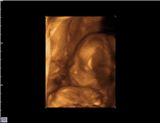

BabyBoy20W.jpg

BabyBoy

Before born